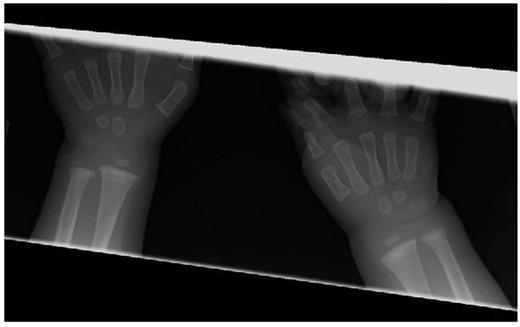

Case: Though subtly symptomatic from birth, our patient was diagnosed with CAT syndrome at four months of age after an episode of grossly bloody stools. After failed therapy with corticosteroids and vincristine, the patient was given bevacizumab 10mg/kg/dose every two weeks for four doses with excellent clinical response. After her fourth dose, a chest radiograph revealed incidental, asymptomatic metaphyseal lesions of the humeri. A complete bone survey revealed similar lesions in the metaphyses of nearly all of her long bones. (Figure 1) Given preclinical data suggesting these lesions could result from the use of VEGF inhibitors, bevacizumab was discontinued. All metaphyseal lesions subsequently resolved. (Figure 2) To our knowledge, this is the first report of bony toxicity in a human receiving bevacizumab. A thorough literature review on VEGF inhibitors revealed no reported cases of metaphyseal lesions or stunted growth in humans receiving VEGF inhibitors. Animal studies, however, suggest this may be possible. Growth plates consist of avascular cartilage that is eventually replaced by bone. This process requires invasion of the cartilage with metaphyseal blood vessels and has been shown to be directed by a VEGF gradient (